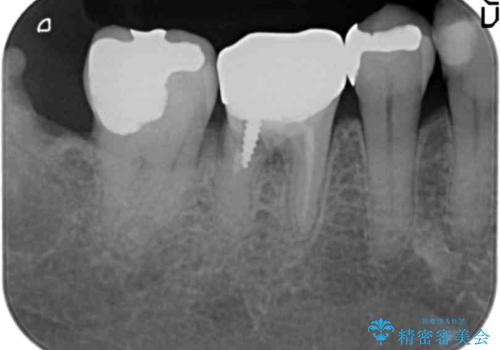

- 奥歯の違和感を主訴に来院された患者様です。

右下の銀歯(右下6)を除去したところ、虫歯が深く保存不可能な状態でした。

ブリッジ、インプラント、入れ歯の3つの選択肢を提案したところ、ブリッジをご希望されました。

抜歯後十分に歯肉の治癒を待ったのち、ブリッジによる補綴治療を行いました。